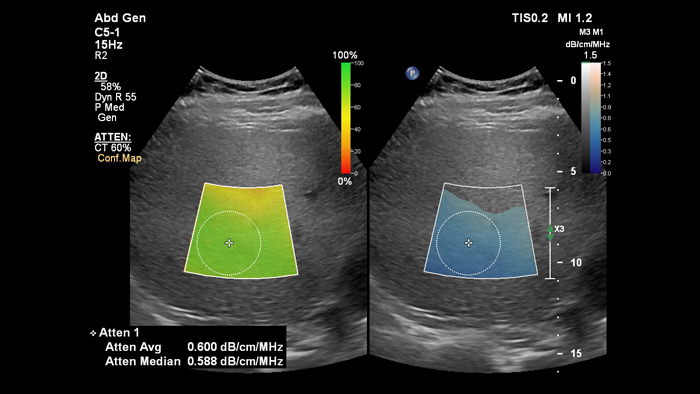

Attenuation Imagingでは、肝実質によって吸収される音の減衰係数を計算することにより、肝臓に存在する脂肪の量を測定できます。この方法では定量的な減衰パラメータが得られ、脂肪肝患者のマネージメントをサポートします。

Attenuation Imaging